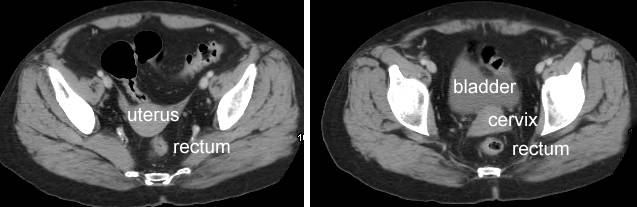

- normal rectal CT scan, normal

rectal CT,

normal

normal female CT

-

normal female CT, normal

rectal CT (female)